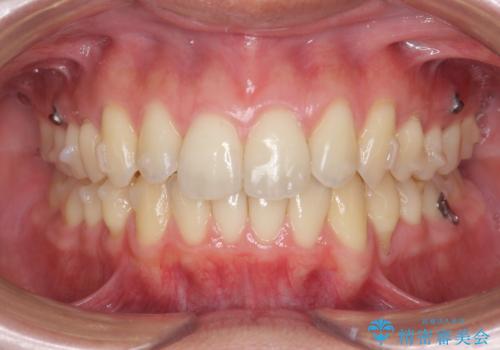

以上のような問題点をマウスピース矯正インビザラインとマイクロインプラントを用いて矯正治療を行い改善して行きます。

20時間以上のマウスピース装着、ゴムかけを遵守していただいたおかげでしっかりと噛み合わせ、がたつきの改善を行うことができました。